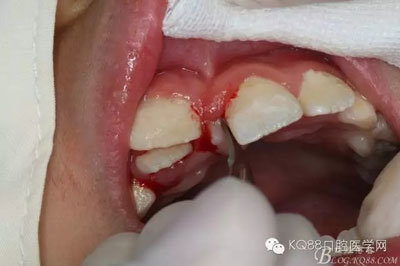

圖5.唇側(cè)無痛浸潤麻醉

圖6.腭側(cè)無痛浸潤麻醉